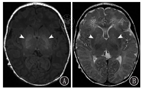

后期随访的MRI可以从病理学角度判定现有的临床症状(图17),上列显示T2WI轴向;下列显示T2WI运动束冠状面的损伤[16]。

图17

后期随访的磁共振成像结果 A:轻度不对称形式,涉及右侧运动束(大箭头所示),小箭头显示额部神经胶质增生(6岁,左侧单侧痉挛性脑瘫,GMFCS Ⅰ级);B:轻度对称性,涉及两侧运动束,箭头指示室周神经胶质增生(3岁,双侧痉挛性脑瘫,GMFCS Ⅰ级);C:不止双侧神经胶质增生的严重形式(箭头),还有组织的损失(6岁,双侧痉挛性脑瘫,GMFCS Ⅴ级)

Figure 17

Magnetic resonance imaging results of late follow-up A:a mild,but very asymmetrical form,involving the motor tract only on the right side,indicated by the big arrow,while the small arrow indicates frontal gliosis (age 6 years old,unilateral spastic CP on the left side,GMFCS level Ⅰ);B:a mild symmetrical form,involving motor tracts on both sides,the arrow indicates the periventricular gliosis (3 years old,bilateral spastic CP,GMFCS level Ⅰ);C:a severe form with not only bilateral gliosis,indicated by the arrows,but also tissue loss (6 years old,bilateral spastic CP,GMFCS level Ⅴ)